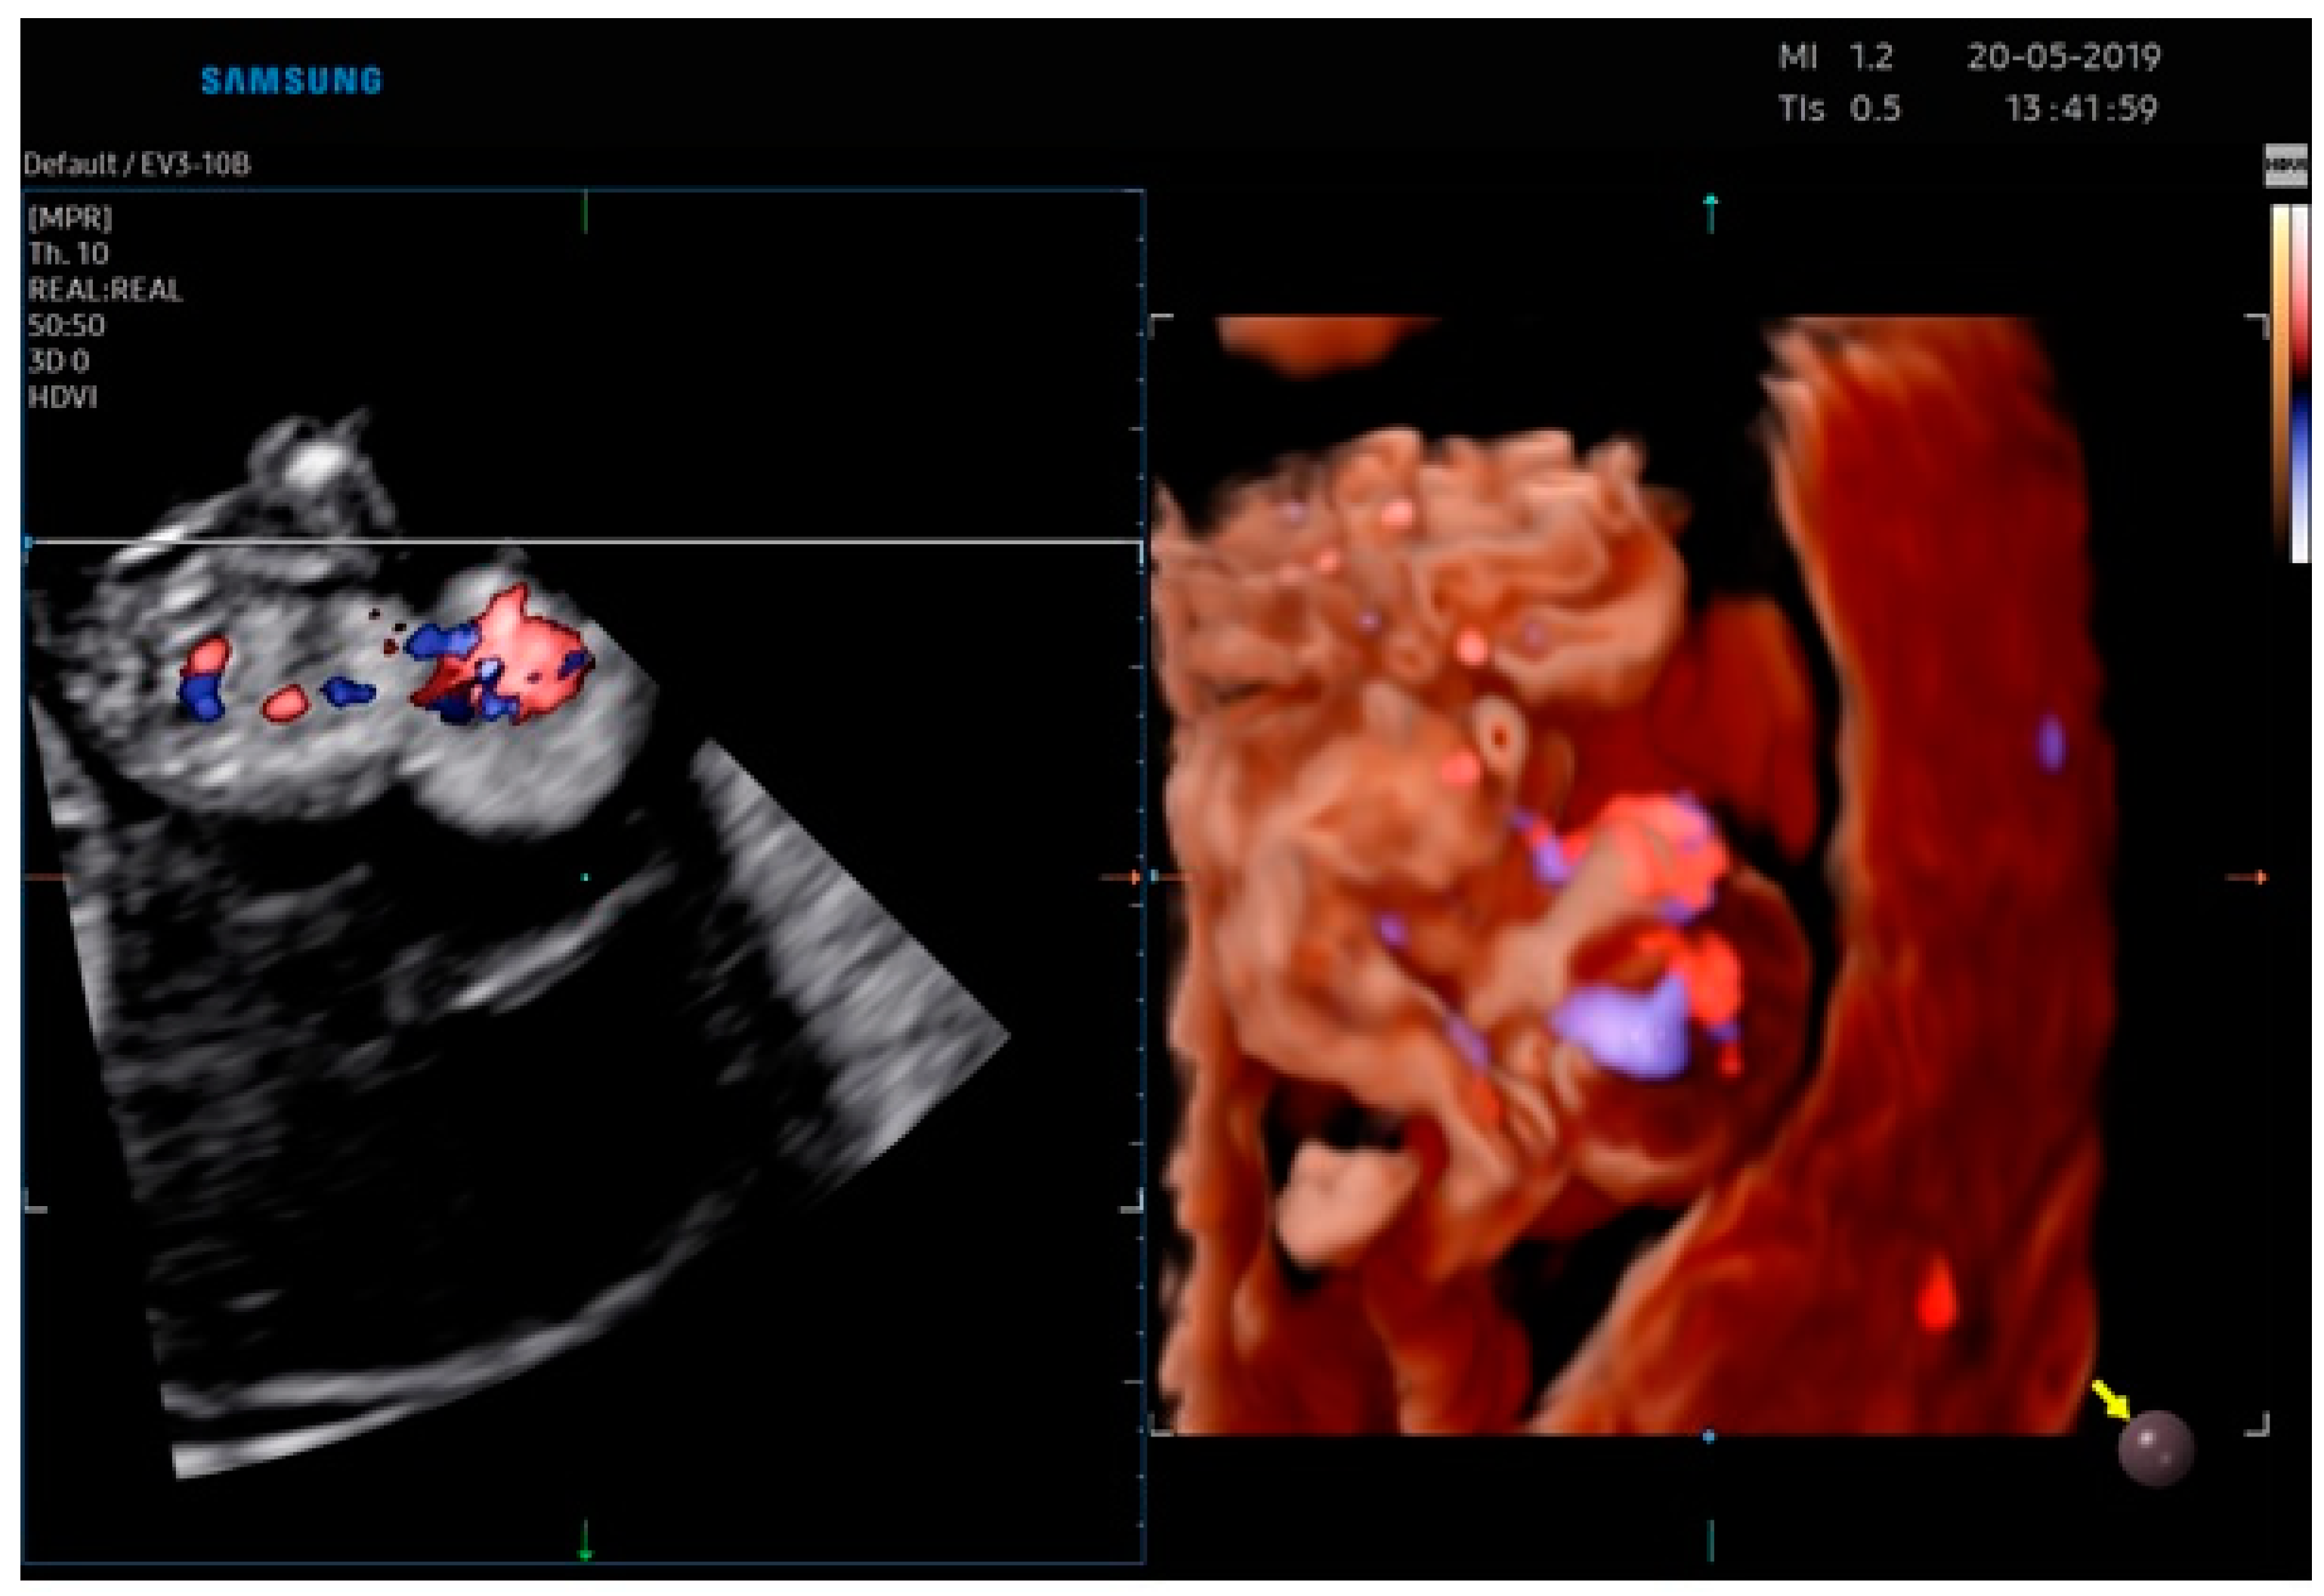

Body Stalk Anomaly Complicated by Ectopia Cordis: First-Trimester Diagnosis of Two Cases Using 2- and 3-Dimensional Sonography

2.1. Case Report 1

2.2. Case Report 2